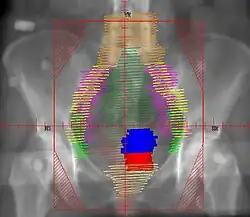

Example of a lateral radiation therapy treatment field for Stage IB2+ Cervix used at Tufts/Brown residency program. Actual patient contours should guide field design and AP/PA vs. 4F decision.

• Superior border: same as AP field

• Inferior border: same as AP field

• Anterior border: ~1cm anterior to symphysis pubis

• Posterior border: cover entire sacrum to ensure coverage of presacral lymph nodes

• Red: cervix; Blue: uterus; Khaki: bladder; Brown: rectum

• Orange: common illiac LNs; Yellow: external illiac LNs; Light Green: obturator LNs; Purple: internal illiac LNs; Dark Green: presacral LNs